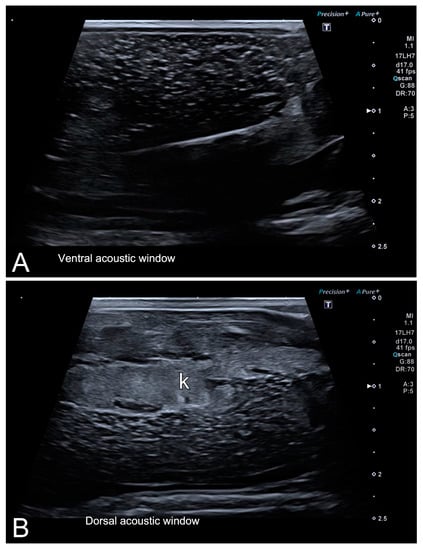

3.2. Ultrasonography